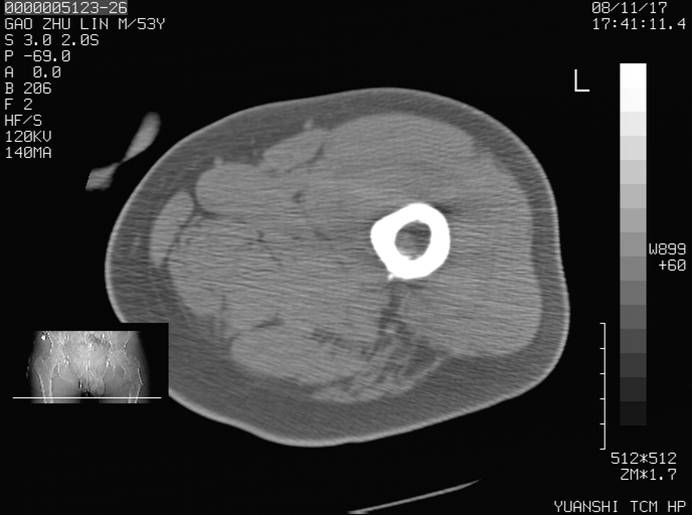

标题: CT16696:M53Y,左股骨上段骨折。 [打印本页]

标题: CT16696:M53Y,左股骨上段骨折。

左股骨上段粉碎性骨折

左股骨上段粉碎性骨折;建议上传骨窗看看是不是病理性的啊!

左股骨上段粉碎性骨折,不排除病理性骨折可能。

考虑骨肉瘤伴病理骨折

考虑:骨肉瘤伴病理骨折.

病理性骨折,考虑转移所致.

左股骨上段粉碎性骨折,不排除病理性骨折可能